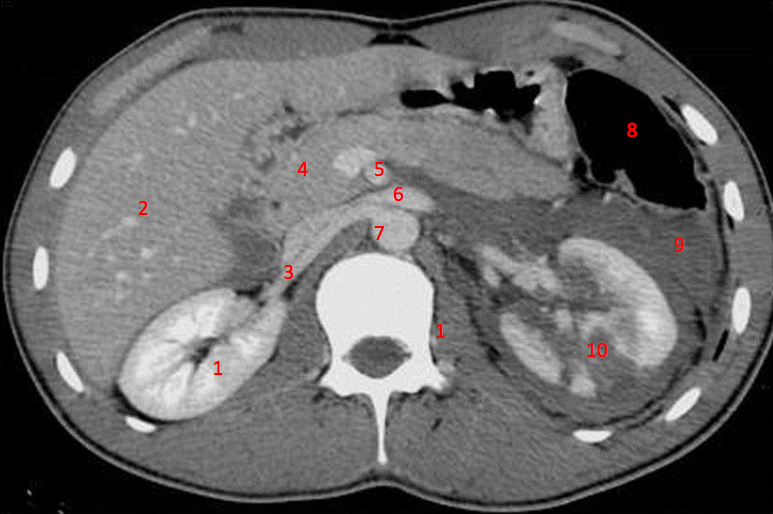

Number 1?

R Kidney

Number 2?

IVC

Number 8?

Body of thoracic vertebra

Descending colon

Number 10?

Rt rib

Number 9?

Superior mesenteric artery